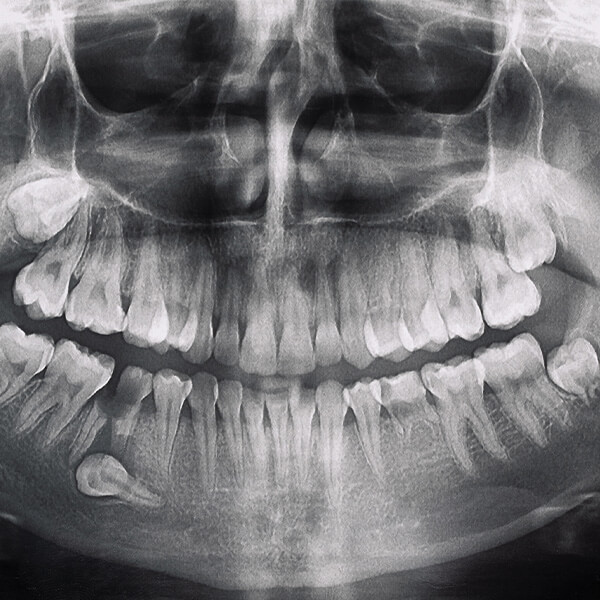

Pierwszym krokiem w leczeniu zatrzymanych zębów jest szczegółowa konsultacja stomatologiczna i diagnostyka. Wykonujemy panoramiczne zdjęcia rentgenowskie oraz stożkową tomografię komputerową, aby dokładnie ocenić położenie zatrzymanego zęba oraz jego wpływ na otaczające tkanki i struktury zębowe.

Zanim przystąpimy do zabiegu, pacjent przechodzi szczegółową konsultację stomatologiczną, która obejmuje badanie jamy ustnej oraz diagnostykę obrazową (pantomogram, tomografia komputerowa). Na tej podstawie opracowujemy indywidualny plan leczenia.

Pierwszym krokiem w przygotowaniu do leczenia protetycznego jest szczegółowa konsultacja stomatologiczna. Podczas tej wizyty przeprowadzamy wywiad medyczny, aby zrozumieć historię zdrowia pacjenta oraz jego oczekiwania i potrzeby. Następnie wykonujemy szereg badań diagnostycznych, w tym zdjęcia rentgenowskie (Pantomogram, RVG) oraz tomografię komputerową, aby dokładnie ocenić stan jamy ustnej, kości i tkanek miękkich.

- Przed przystąpieniem do zabiegu wykonujemy szczegółowe badania diagnostyczne, w tym zdjęcia rentgenowskie i tomografię komputerową, aby dokładnie ocenić stan korzenia zęba i otaczających tkanek.